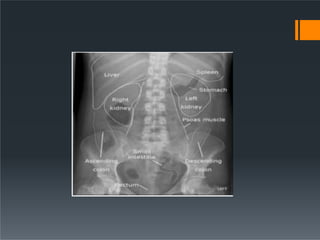

Abdominal Organs

ď‚§ Liver

ď‚§ right upper quadrant

ď‚§ extends to the hemidiaphragm and past the midline

 Chilaiditi’s syndrome

ď‚§ Spleen

ď‚§ left upper quadrant

ď‚§ extends to the hemidiaphragm

ď‚§ Its lower pole may be outlined by fat

ď‚§ Measurement of its length from the dome of the diaphragm

to the tip. This is usually less than 14 cm

ď‚§ Relationship of the spleen to the ninth, tenth and eleventh

ribs

ď‚§ Normal gallbladder or biliary system are not visible. Gas

ď‚§ Psoas muscle

ď‚§ symmetrical triangles either side of the lumbar spine

ď‚§ Stomach

ď‚§ left of midline, beneath hemidiaphragm

ď‚§ Kidneys

ď‚§ sit on the psoas muscles at level of T12 to L3

Abdominal Organs  Liver right upper quadrant  extends to the hemidiaphragm and past the midline  Chilaiditi’s syndrome  Spleen  left upper quadrant  extends to the hemidiaphragm  Its lower pole may be outlined by fat  Measurement of its length from the dome of the diaphragm to the tip. This is usually less than 14 cm  Relationship of the spleen to the ninth, tenth and eleventh ribs

 Stomach  leftof midline, beneath hemidiaphragm  Gastric fundus fixed in location: within 2.5cm of left hemidiaphragm.  sometimes just a small volume of gas in the fundus  do not mistake a rim of gas for pneumoperitoneum  Kidneys  sit on the psoas muscles at level of T12 to L3  often just see the rounded lower pole  Perirenal fat often makes part or all of the renal outlines visible  Renal size is variable, with a normal range of 10 – 15 cm on a radiograph or approximately three-and-a-half vertebral bodies in height  The left kidney is usually larger, but a difference in size of more than 2 cm is abnormal  The kidneys are relatively larger in the child (approximately four vertebral bodies in height)  Adrenal glands visible only if calcified.